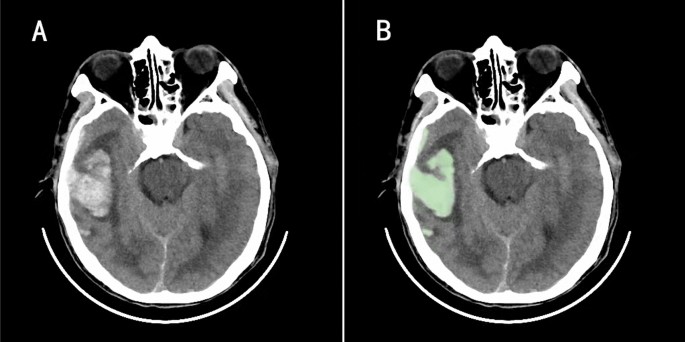

Extracting the patient's cranial CT data within 6 h of admission and measuring the contusion volume by computer-aided software 3D Slicer (version 4.8.0; Harvard University, New York). 3D slicer provides contusion volumes by manually selecting the region of interest, setting thresholds based on Hounsfield units (fixed windows of 110 and 50 HU) to distinguish between the contused portion of the brain and the surrounding normal brain tissue, and automatically summarizing adjacent voxels (Fig. 2A and B). When multiple contusions were present, the total volume was calculated.

On the 3D slicer software, the contusion volume is provided by manually selecting the region of interest, setting the threshold based on the Hounsfield unit (the fixed thresholds of 110 and 50 HU) to distinguish the contusion part from the surrounding normal brain tissue, and automatically summarizing the adjacent voxels (A and B).